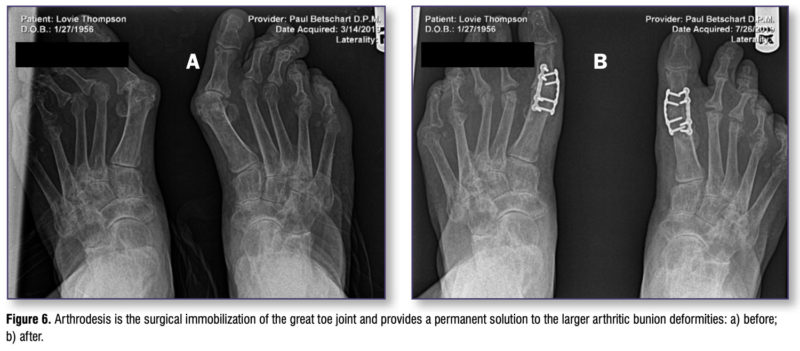

- Arthrodesis (surgical immobilization of a joint): Arthrodesis of the great toe joint is the only permanent solution to the arthritic bunion deformity. It can also provide 3-plane correction and stability of the first ray, making it useful with larger deformities. Advanced fixation techniques allow for immediate protected weightbearing in a CAM walking boot. Recovery time is similar to the Lapidus procedure. The functionality of the fused great toe joint is actually very good – this procedure has even been performed successfully in high-level athletes. The biggest problem with the fused great toe joint is the limitation of the ability to wear higher heeled shoes. See Figure 6.